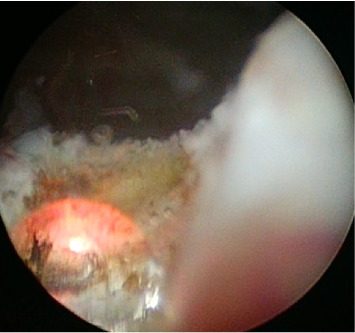

Abstract Image